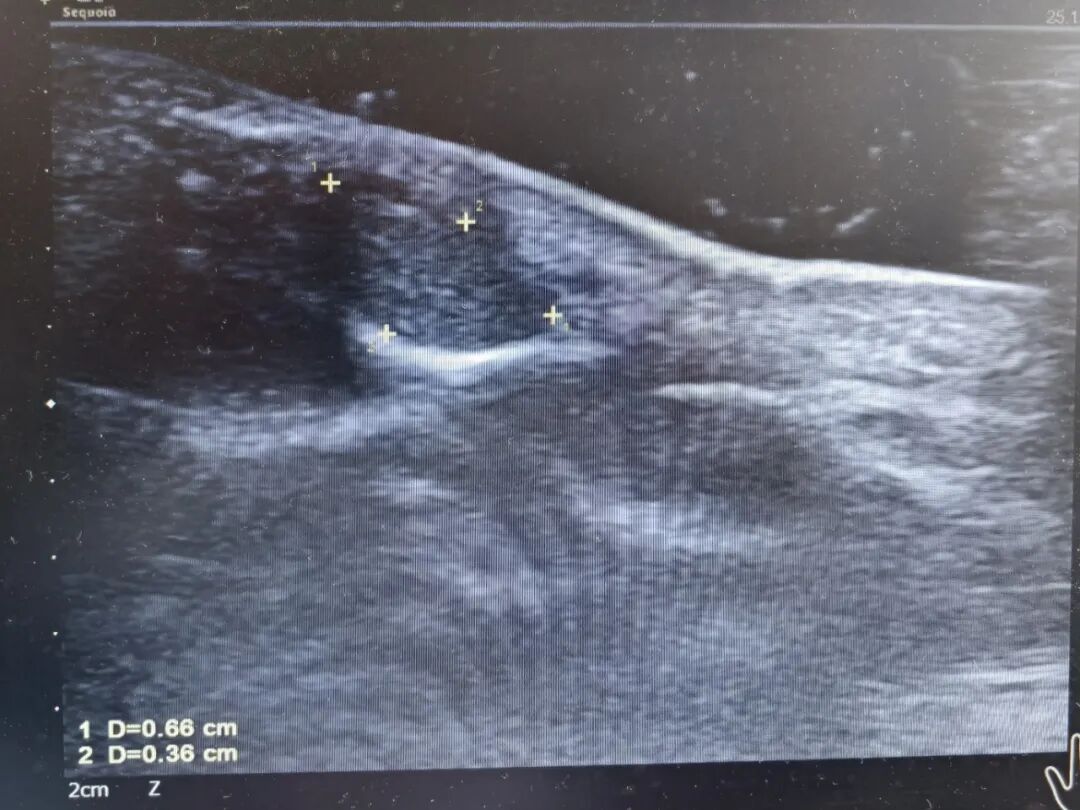

彩超结果印证了医师们的判断:指甲下的肿瘤直径有0.8cm大,需要进行手术治疗。